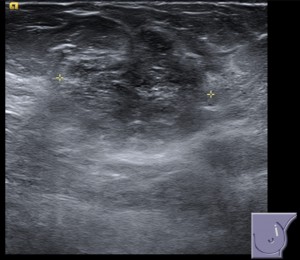

Ante estos hallazgos, la prueba complementaria a realizar sería la ecografía, para valorar mejor el nódulo. Observamos un nódulo heterogéneo, isoecogénico y palpable en CSE MI, de márgenes parcialmente definidos, de alta sospecha de malignidad y asociados a cambios inflamatorios regionales.

El diagnóstico fue un nódulo BIRADS 4 en CSE MI, palpable, con cambios inflamatorios asociados en ecografía. Se realizó una BAG. Se necesitarían los resultados de anatomía patológica para poder dar un diagnóstico preciso.